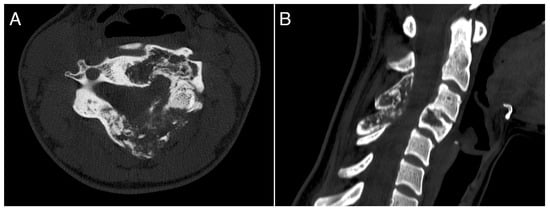

A 26-year-old female with a massively lytic lesion in C4 showed consistent ossification after seven months of treatment (Figure 2 and Figure 3). She chose to discontinue denosumab after 20 administrations due to being asymptomatic and being at her fertile age. However, ten months after stopping the medication, she experienced severe neck and upper left pain, leading her to seek urgent medical attention at the emergency department of our clinic. CT and MRI showed a local recurrence of the ABC in C4 (Figure 4 and Figure 5). She then received a “re-challenge” treatment with denosumab according to the above-mentioned protocol, and the treatment is still ongoing. At the last follow-up, 20 months after being on denosumab with a monthly schedule, the patient was asymptomatic, and the last CT showed good ossification of C4 (43 months follow-up from the first treatment).

Figure 5. CT scan performed at last follow-up 24 months after denosumab re-challenge. (A): axial view; (B): sagittal view.